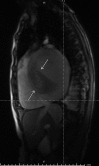

An Audaciously Aneurysmal Atrium

Keywords: Echocardiography; Imaging; Mitral stenosis; Rheumatic heart disease.